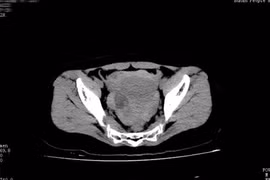

Đau bụng âm ỉ thiếu nữ 16 tuổi phát hiện u buồng trứng vỡ

Nang Degraff (nang trứng sinh lý) vỡ sẽ tự cầm máu. Nếu mạch máu bị tổn thương, máu không thể tự cầm cần được phẫu thuật khẩn cấp.